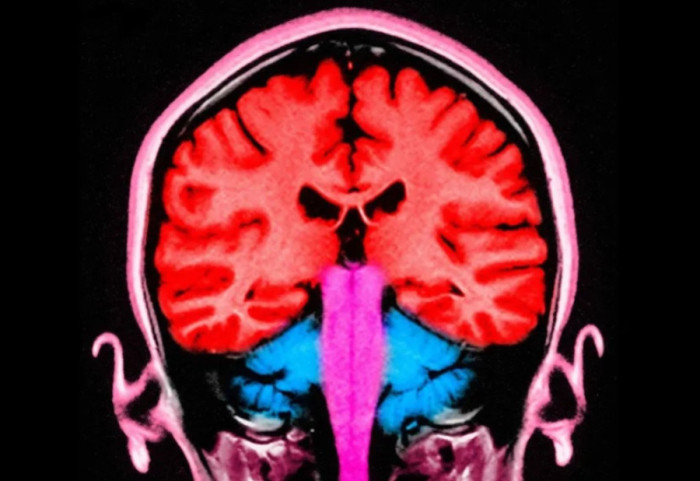

Truri i njeriut nuk zhvillohet në mënyrë të qëndrueshme, por kalon në pesë faza të dallueshme përgjatë jetës, me pika kyçe ndryshimi në moshat 9, 32, 66 dhe 83 vjeç, sipas një studimi të ri nga Universiteti i Cambridge.